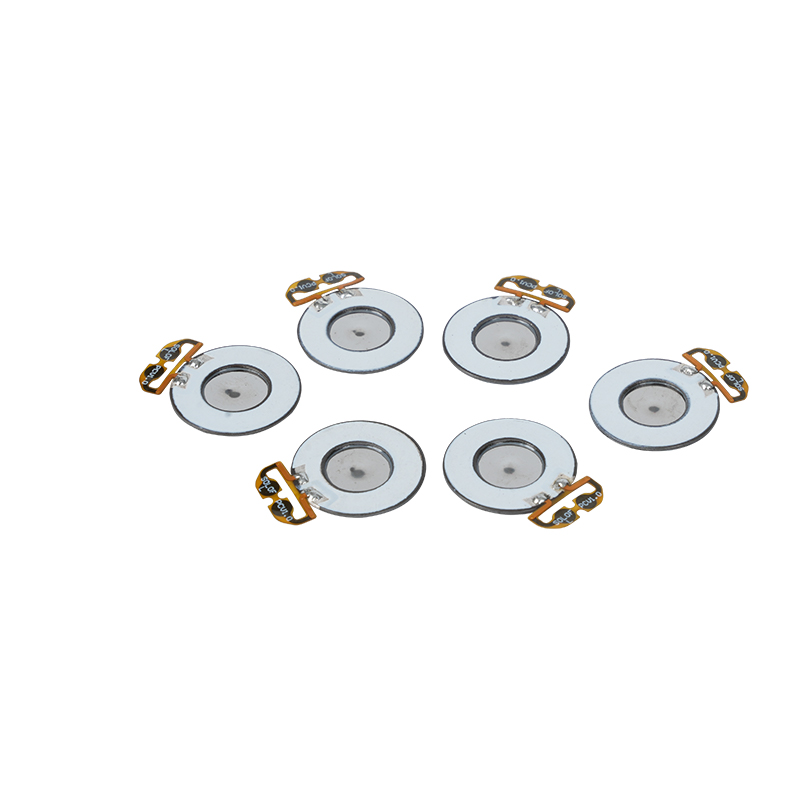

Le compresse di nebulizzatore a rete medica sono componenti di precisione utilizzati nei dispositivi medici per convertire farmaci o soluzioni in minuscole particelle di aerosol per il trattamento di vari disturbi respiratori come l'asma e la broncopneumopatia cronica ostruttiva (BPCO), ecc. mediante inalazione. Il design e la scelta dei materiali del foglio del nebulizzatore sono fondamentali per garantire un'efficace somministrazione del farmaco e il comfort del paziente. Il foglio del diaframma inossidabile viene perforato con migliaia di minuscoli fori a rete da 2-3 μm nella lamiera di acciaio attraverso la tecnologia di perforazione laser in un processo laser di precisione, quindi è strettamente legato al foglio rotondo in ceramica piezoelettrica, che converte la frequenza di risonanza del foglio piezoelettrico in energia di vibrazione ad alta frequenza attraverso il segnale di uscita della scheda driver PCB e si rompe rapidamente il farmaco liquido in fini particelle di aerosol. Queste goccioline sono anche chiamate dimensione mediana delle particelle, quando la percentuale mediana delle particelle D50 raggiunge >60% o più, le particelle saranno abbastanza piccole da poter raggiungere in profondità i polmoni fino alla superficie degli alveoli con la respirazione, migliorando così l'efficienza di assorbimento del farmaco e l'effetto terapeutico. Il foglio per nebulizzatore a micro rete Medical Mesh ha principalmente diverse forme, il foglio per nebulizzatore a micro rete in acciaio inossidabile, il foglio per nebulizzatore medico al nichel palladio, il foglio per nebulizzatore medico in polimero PI e così via. Tutto quanto sopra avviene attraverso la conversione dell'energia di vibrazione ceramica piezoelettrica per ottenere l'effetto di atomizzazione.

La poliimmide (Poliimmide) denominata PI, è la migliore prestazione completa dei materiali polimerici organici, ha un'eccellente stabilità chimica e può resistere alla corrosione di una varietà di farmaci, per garantire l'uso a lungo termine delle prestazioni delle compresse atomizzate. Inoltre, anche la stabilità termica del film polimerico PI è eccellente, con un uso a lungo termine nell'intervallo di temperature -200 ~ 300 ° C, elevato isolamento, protezione ambientale e non tossicità, poiché un materiale tecnico speciale, ampiamente utilizzato nelle membrane di separazione a cristalli nanoliquidi della microelettronica aerospaziale e in altri campi, è stato incluso nel 21° secolo dai paesi come uno dei materiali tecnici più promettenti, e non è facile da deformare nel processo di disinfezione ad alta temperatura, per garantire che il prodotto venga riutilizzato! Per il sesso e la sicurezza, utilizziamo la tecnologia laser per la perforazione laser, la pellicola PI impiantata tra l'acciaio inossidabile e la lamiera piezoelettrica, l'uso della tecnologia ultrasonica ceramica piezoelettrica in modo che le goccioline atomizzate attraverso la pellicola PI si disperdano nell'atomizzazione di particelle da 3 ~ 4 μm per l'inalazione di nebulizzazione medica, la sicurezza apprezzata dalla maggior parte degli utenti, fatta del nebulizzatore con il Il vantaggio principale di PI è l'assenza di intasamenti, la parete interna del foro liscia e arrotondata, nessun residuo di liquido, l'atomizzazione fine e stabile. L'atomizzazione è delicata e stabile. Le compresse di nebulizzatore con film PI possono prevenire efficacemente i residui di farmaco, ridurre il rischio di contaminazione incrociata. Nell'applicazione pratica, si sono riflesse anche le caratteristiche di basso consumo energetico delle compresse di nebulizzatore a membrana polimerica PI, in sintesi, le compresse di nebulizzatore a membrana polimerica PI con le sue eccellenti prestazioni e vantaggi di progettazione, sono diventate una parte indispensabile del campo della terapia di nebulizzazione medica.

La ceramica piezoelettrica senza piombo è conosciuta come la "perla" dell'industria piezoelettrica, il futuro sostituirà gradualmente la ceramica piezoelettrica a base di piombo in tutti gli aspetti, che ha già le stesse prestazioni piezoelettriche, e il foglio piezoelettrico a base di piombo. È completamente atossico, innocuo, sicuro ed ecologico, non contiene piombo, antimonio e altri metalli pesanti e altri elementi soggetti a restrizioni Rohs, elevata temperatura Curie Tc-328 ° C, perdita elettrica molto bassa TangentLoss Pertanto, il chip di atomizzazione medica piezoelettrica senza piombo ha un grande valore commerciale e un valore universale, la ceramica piezoelettrica senza piombo veramente atossica e rispettosa dell'ambiente, oltre alle prestazioni piezoelettriche non inquinanti e commisurate alla ceramica a base di piombo, diventerà una popolare ceramica piezoelettrica rispettosa dell'ambiente. Dopo anni di ricerca e sviluppo, dopo continui test e sperimentazioni, l'azienda è riuscita a realizzare il chip di atomizzazione medica senza piombo per ottenere la stessa quantità di atomizzazione del chip di atomizzazione a base di piombo e gli stessi requisiti di particelle di diametro. Il chip nebulizzatore a rete medica senza piombo, sicuramente brillerà e otterrà una vasta gamma di scenari di utilizzo.

Con la produzione di inquinamento ambientale da parte delle persone e il crescente sviluppo di prodotti umidificatori, il foglio di atomizzazione in microrete di acciaio inossidabile è diventato il componente principale dei moderni umidificatori con la sua alta efficienza e risparmio energetico, bassa rumorosità e lunga durata. Migliora efficacemente l'efficienza dell'umidificazione raffinando le molecole d'acqua in minuscole nebbie d'acqua, riducendo al contempo il consumo di acqua. Inoltre, l'utilizzo di compresse atomizzatore a microrete riduce l'inquinamento ambientale perché non richiede additivi chimici o riscaldamento per ottenere l'effetto di umidificazione desiderato. Con il continuo progresso della tecnologia, le prestazioni delle compresse di atomizzazione a microrete stanno migliorando, rendendo gli umidificatori più intelligenti e umanizzati e soddisfacendo la ricerca da parte dei consumatori di una sana qualità della vita.